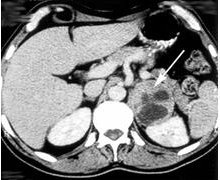

In der bildgebenden Diagnostik steht die Computertomografie an erster Stelle, da der Nachweis von Nebennierentumoren schon ab einer Größe von 5 mm gelingt und bei 2 cm hoch sensitiv ist. Im Ultraschall lassen sich erst größere Tumore nachweisen, die normale Nebenniere ist nicht zu erkennen. Die Kernspintomografie eignet sich hingegen gut für die Darstellung von Phäochromozytomen. Die selektive Blutentnahme aus den Nebennierenvenen dient der hormonellen Charakterisierung und Aktivitätsbestimmung von Tumoren. Die Szintigraphie wird vor allem beim Phäochromozytom eingesetzt.